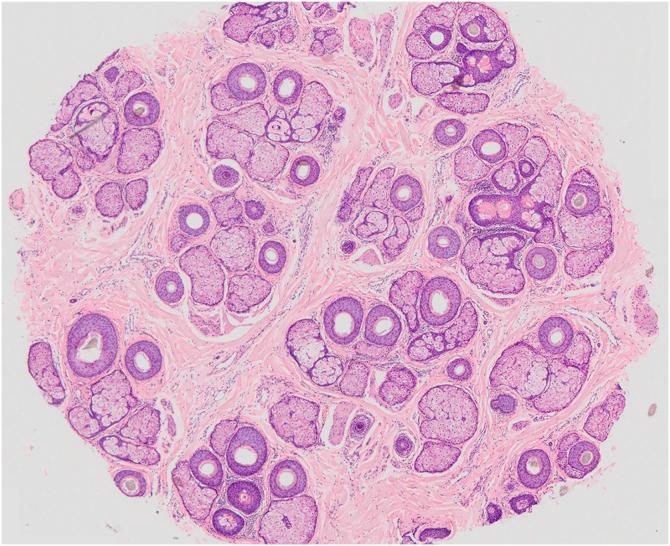

男性雄激素性脱发

Male androgenetic alopecia.

Male androgenetic alopecia (MAA) is quite common and worsens with age, with a significant impact on quality of life, and is increasingly a reason for consultation with a dermatologist. The etiopathogenesis of MAA is multifactorial and genetic and hormonal influences stand out. MAA starts with the process of follicular miniaturization in diverse phenotypic patterns. The diagnosis of MAA is basically clinical and currently corroborated by well-established trichoscopic findings. Despite this, therapeutic options are limited, especially when one considers medications with a high level of scientific evidence. This review aims to help the general dermatologist towards a better understanding of MAA providing a basis for good individualized and judicious therapeutic decisions.

摘要

男性雄激素性脱发(MAA)相当常见,且会随着年龄增长而加重,对生活质量有重大影响,越来越多地成为患者咨询皮肤科医生的原因。MAA的发病机制是多因素的,遗传和激素影响较为突出。MAA始于毛囊在不同表型模式下的微型化过程。MAA的诊断基本上是临床诊断,目前已得到成熟的毛发镜检查结果的证实。尽管如此,治疗选择仍然有限,尤其是当考虑具有高度科学证据的药物时。本综述旨在帮助普通皮肤科医生更好地了解MAA,为做出良好的个体化和明智的治疗决策提供依据。